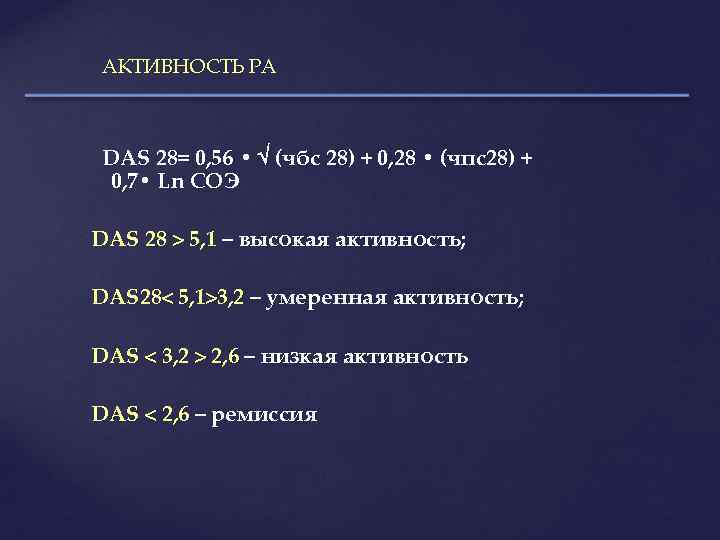

АКТИВНОСТЬ РА DAS 28= 0, 56 • (чбс 28) + 0, 28 • (чпс28) + 0, 7 • Ln СОЭ DAS 28 > 5, 1 – высокая активность; DAS 28< 5, 1>3, 2 – умеренная активность; DAS < 3, 2 > 2, 6 – низкая активность DAS < 2, 6 – ремиссия

АКТИВНОСТЬ РА DAS 28= 0, 56 • (чбс 28) + 0, 28 • (чпс28) + 0, 7 • Ln СОЭ DAS 28 > 5, 1 – высокая активность; DAS 28< 5, 1>3, 2 – умеренная активность; DAS < 3, 2 > 2, 6 – низкая активность DAS < 2, 6 – ремиссия